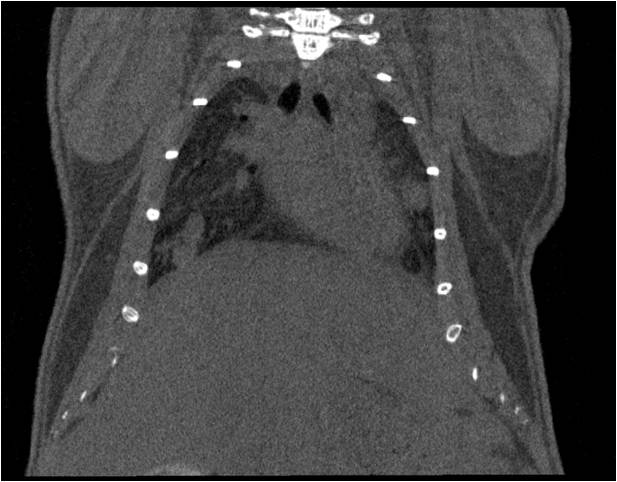

能進(jìn)行呼吸道研究成像,獲取正?;蚣膊顟B(tài)時(shí)肺部及支氣管影像,并對體積等參數進(jìn)行定量分析;

心血管

胸部和心血管的層析成像 胸部和心血管的3D圖像